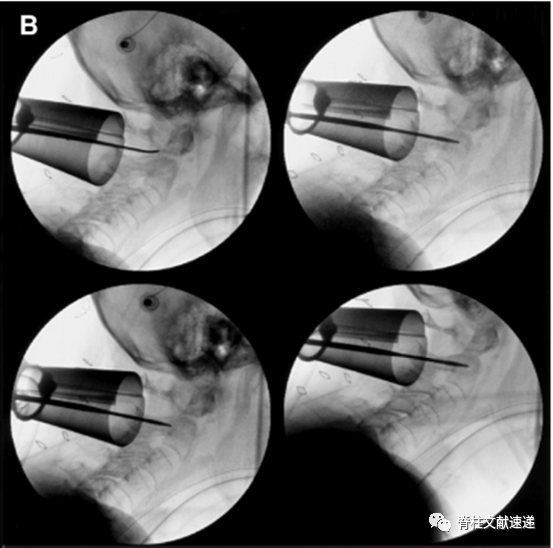

该作者首先进行了4例尸体试验,然后对2例II型齿状突骨折患者进行了微创通道下寰枢椎固定术。下图为一组术中透视影像。

上图:初级扩张通道定位于C2侧块,逐级扩张。

上图:探查C1/2侧块间隙,作出C2椎弓根螺钉钉道。